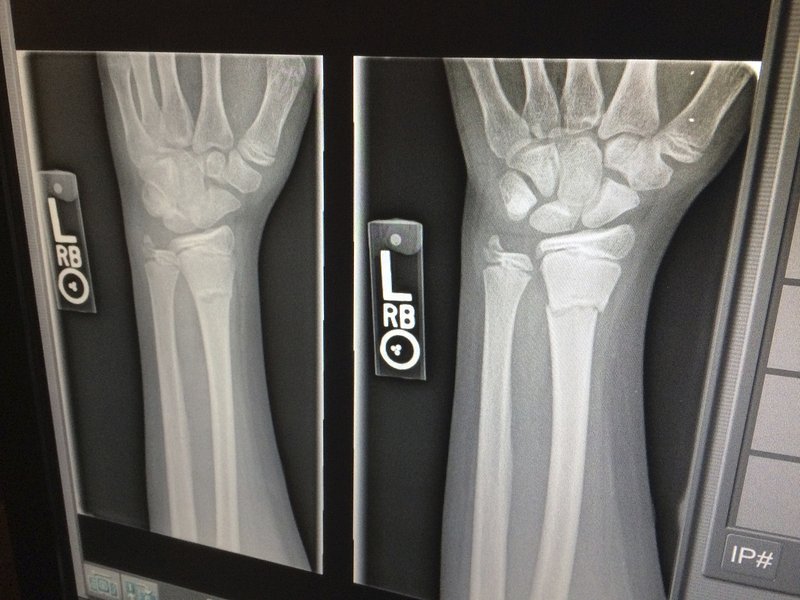

손목 관절염 치료법 바로 알아보기

손목 관절 | 손목 관절염 | 손목 관절염 치료방법 오늘은 손목 관절염 치료방법에 대해서 자세하게 알아보려고 하는데요. 손목 아플때 이런 부분 찾아보시는 경우 무척이나 많습니다. >>>>>> 관절